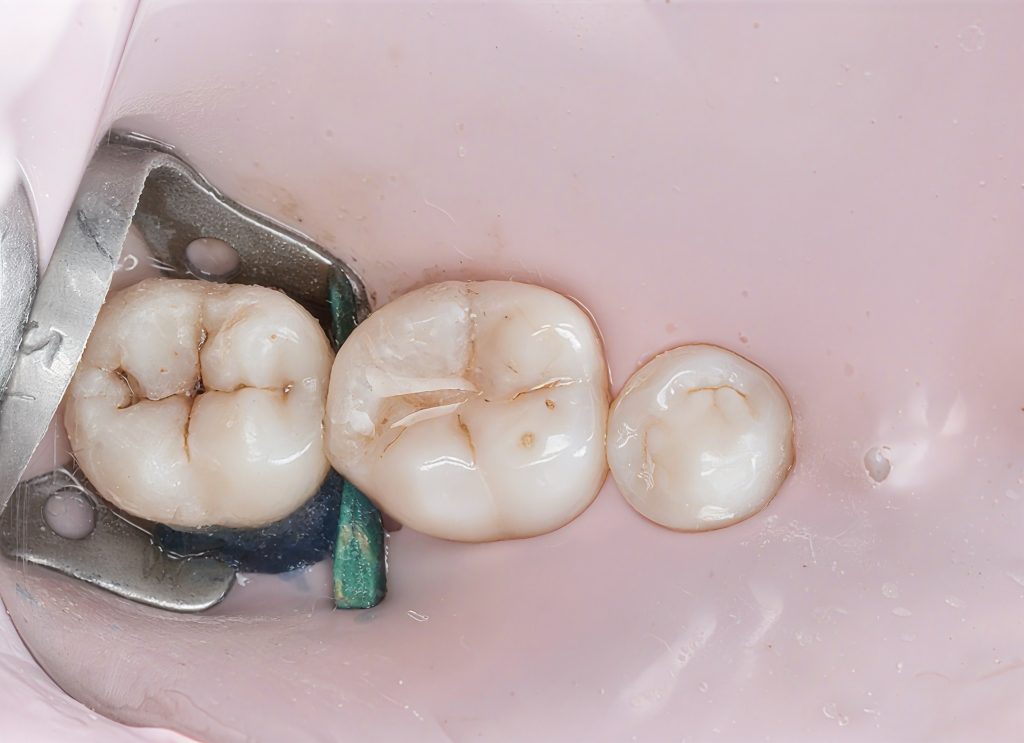

The restored proximal wall regained proper height, contour, and emergence.

4.6 Finishing & Polishing

Finishing was done using:

- Fine diamond for gross adjustment

- Sof-Lex discs for contour

- Silicone polishers for luster

- Final gloss achieved with Diashine (your signature finish)

The occlusion was verified in maximum intercuspation and excursive movements.

- Tight, healthy proximal contact

- Excellent emergence profile that supports papilla health

- Natural occlusal anatomy

- Smooth margins fully blended with adjacent enamel

- Zero postoperative sensitivity

- Patient reported immediate improvement in chewing comfort

The final clinical photos and radiographs reflect a clean, predictable, and biologically respectful restoration.